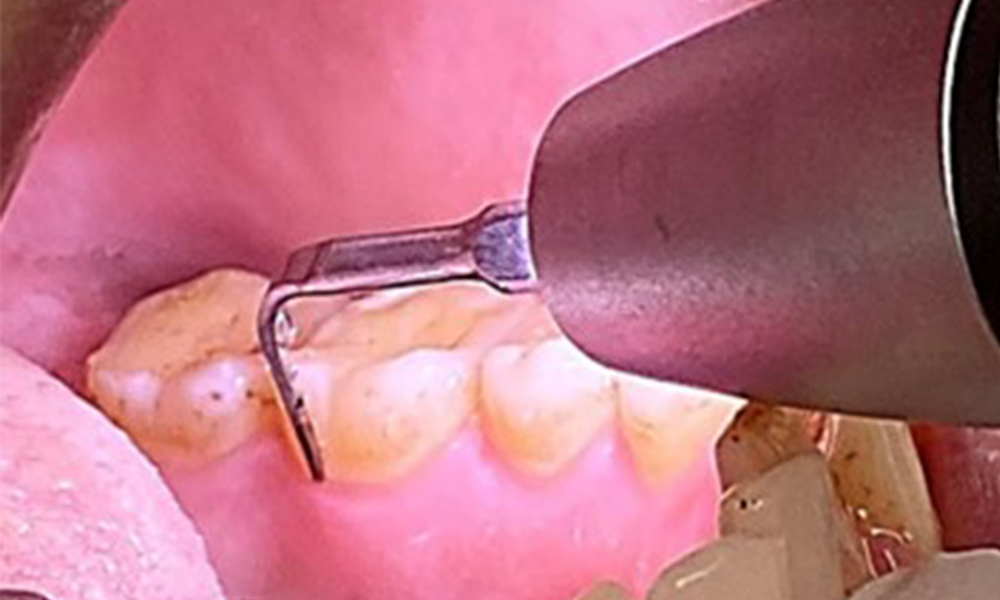

Поради иначе благоприятното общо медицинско състояние, нуждите, определени по време на оралния преглед, ще бъдат решаващи за лечението. От съществено значение ще бъде периодичното определяне на дълбочината на сондиране. Гингивалното кървене намалява при пушачите, поради което клиничната диагноза на пародонтита може да се постави само чрез сондиране (фиг. 7). Поставянето на изключителен акцент върху определянето на индексите на кървене може да замъгли съществуващ пародонтит или гингивит. (5)

Целта е да се контролира рискът от заболяване чрез отстраняване на супрагингивалния и субгингивалния биофилм. Инструментите трябва да бъдат подбрани въз основа на нуждите на пациента. Първо трябва да се отстранят зъбният камък и всички конкременти с помощта на ултразвукови и/или ръчни инструменти (фиг. 10).